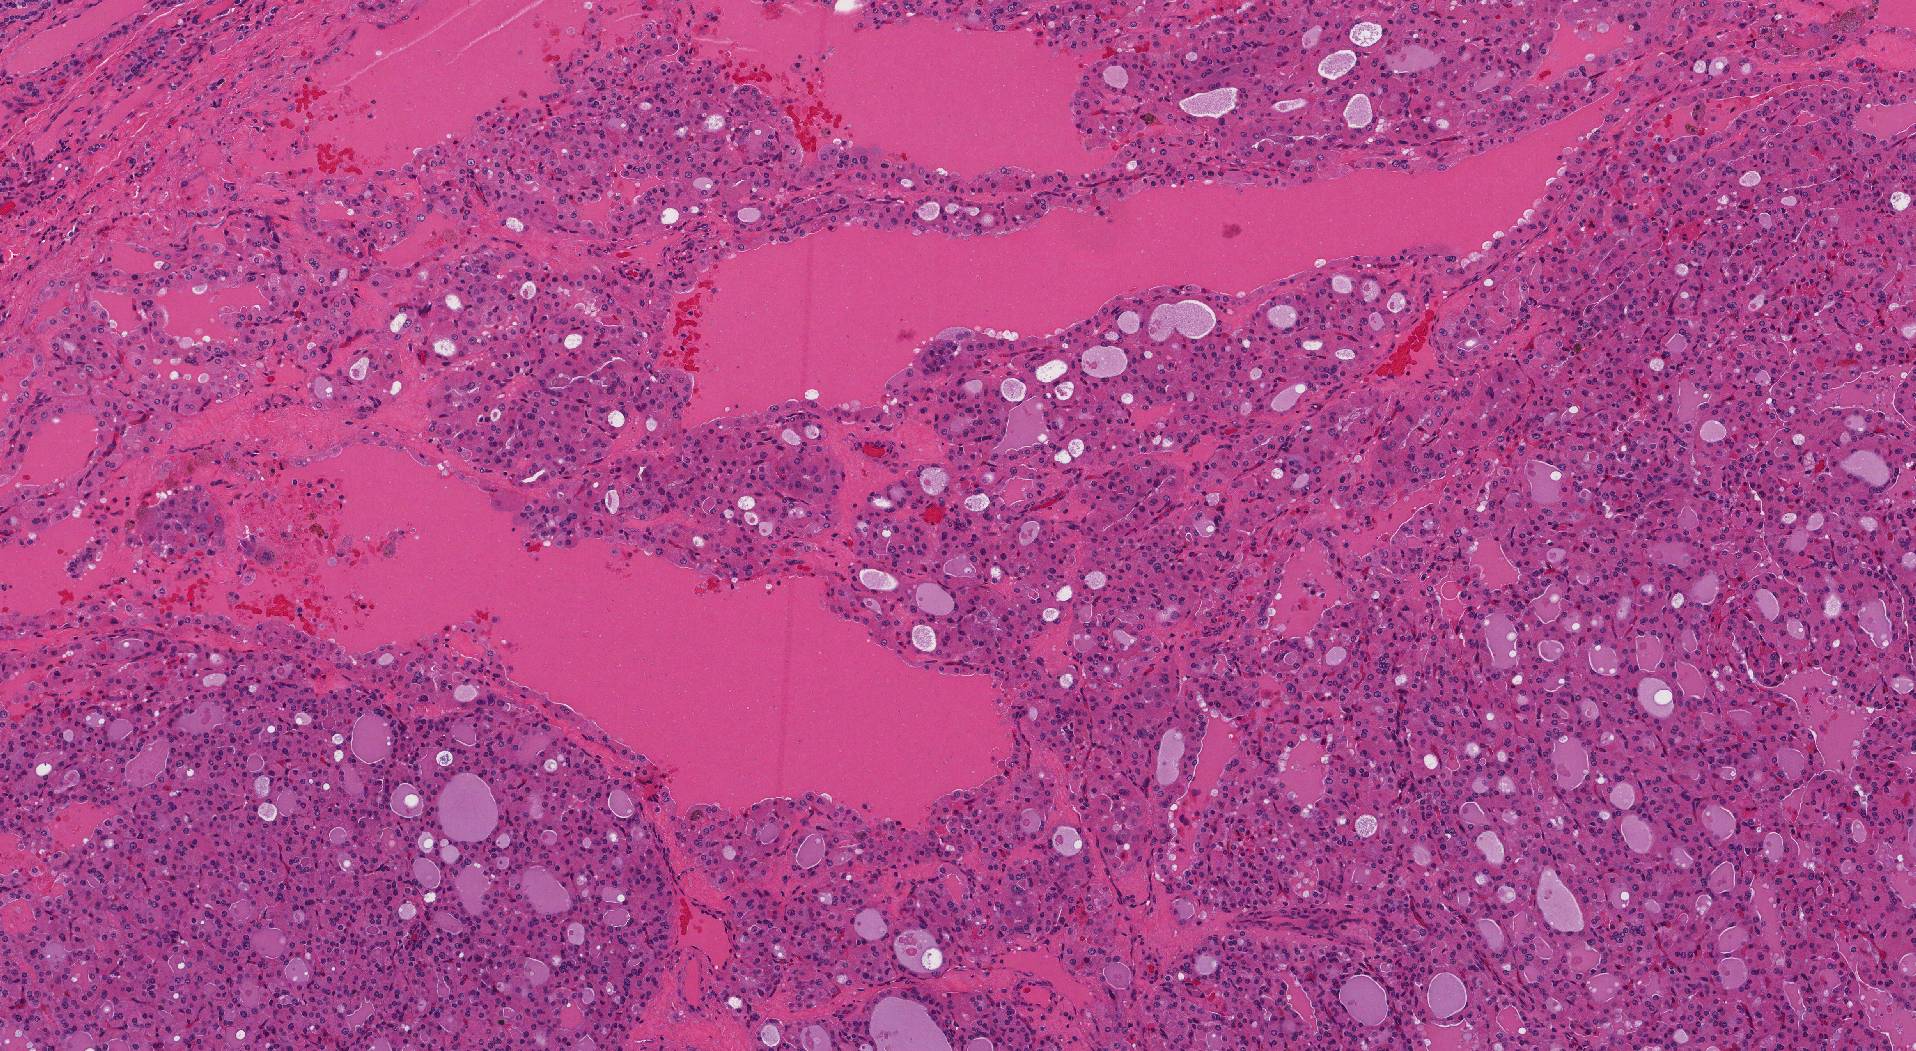

When examined under the microscope, the tumour comprises large pink oncocytic cells. The cells appear pink because the cytoplasm (body of the cell) is full of a cellular part called mitochondria. Oncocytic cells also have a large round nucleus (the part of the cell that holds the genetic material) and a prominent central nucleolus (a clump of genetic material in the middle of the nucleus). The oncocytic cells can connect together to form small round structures called follicles, or they may be in large groups that pathologists describe as a ‘solid pattern’.